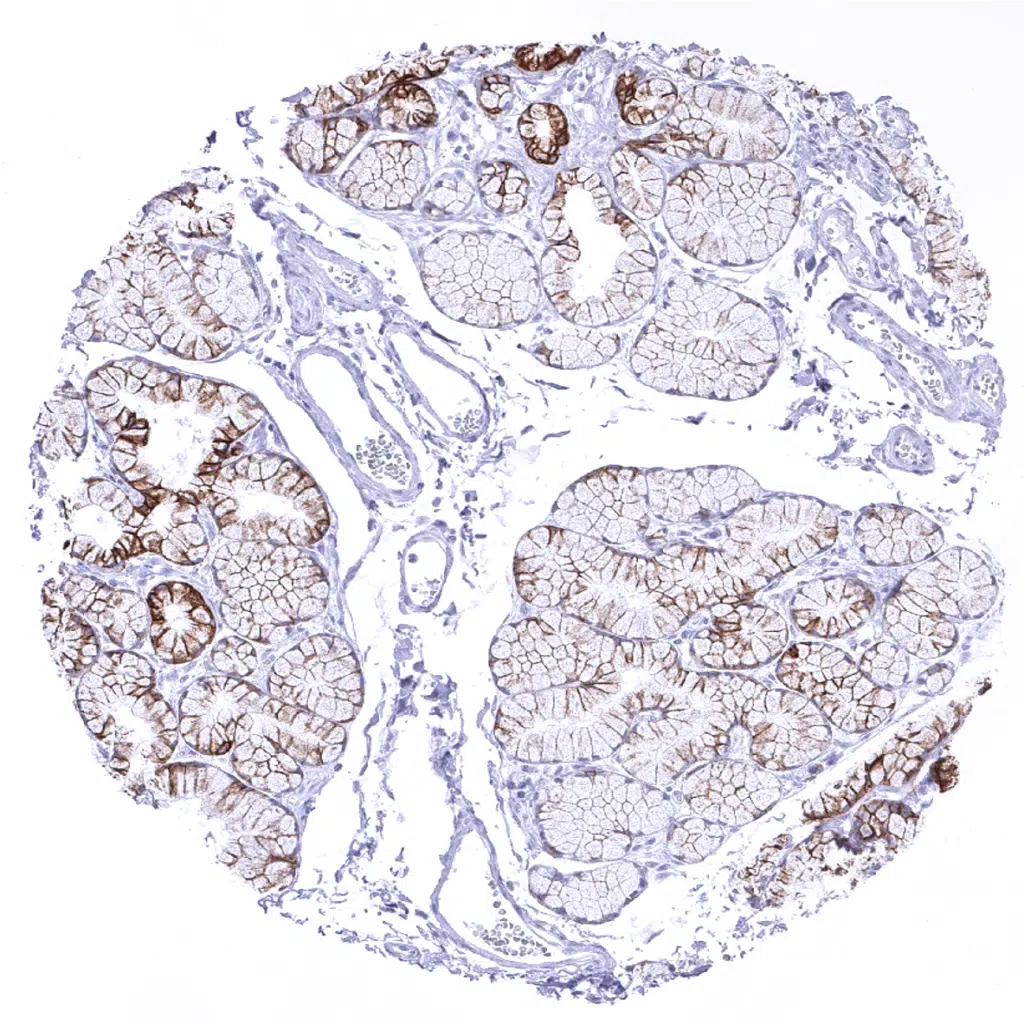

Colon descendens, mucosa - All epithelial cells are Cytokeratin 18 positive.